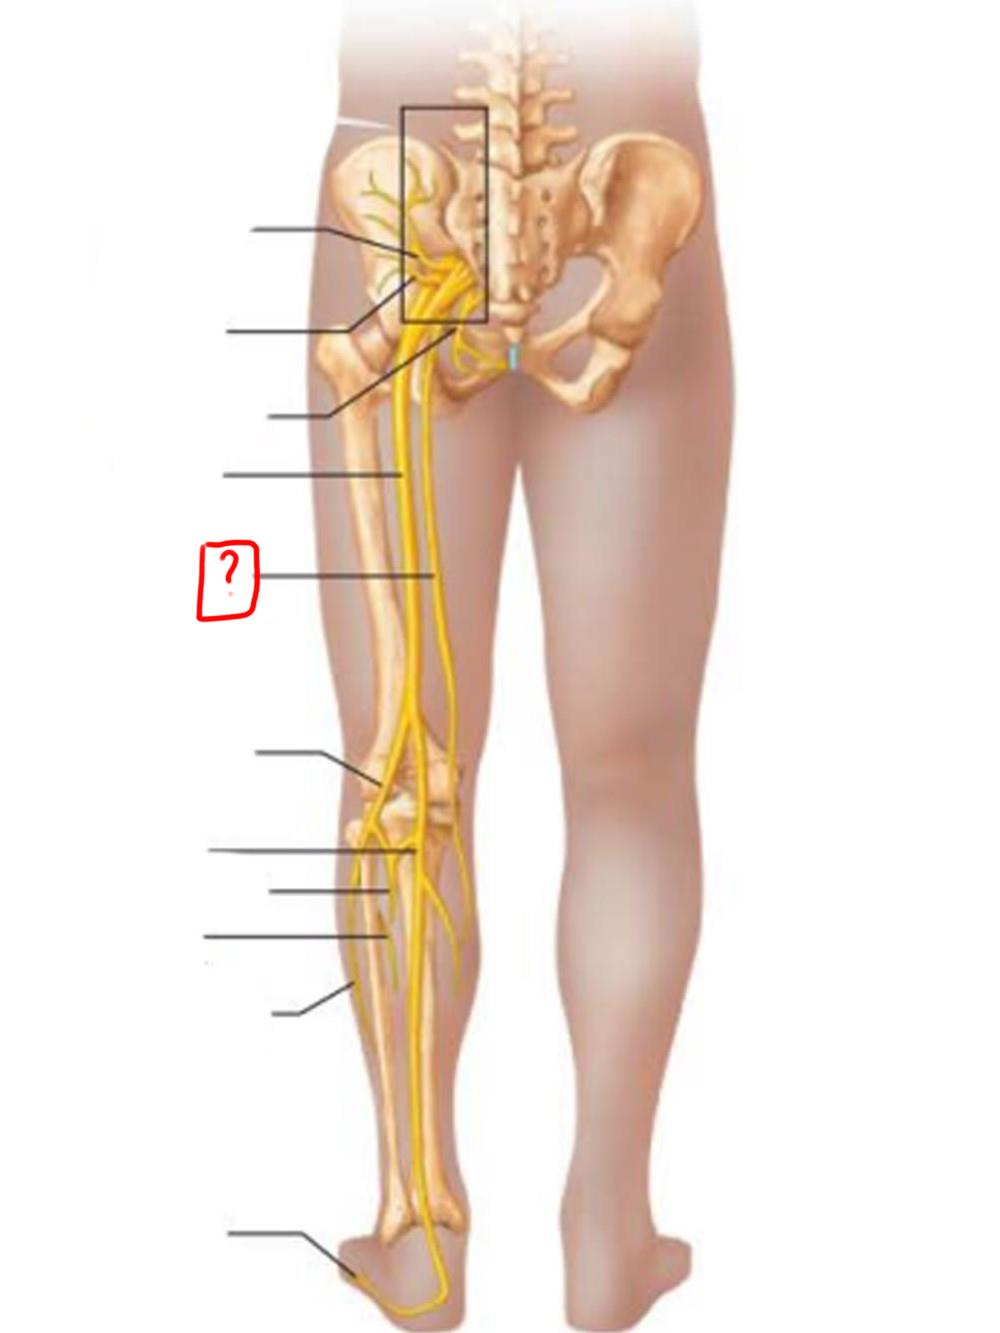

obturator

femoral

lumbosacral trunk

iliohypogastric

ilioinguinal

femoral

lateral femoral cutaneous

obturator

anterior femoral cutaneous

saphenous

superior gluteal

inferior gluteal

pudendal

sciatic

posterior femoral cutaneous

common fibular

tibial nerve

sural (cut)

deep fibular

superficial fibular

plantar branches

superior gluteal

lumbosacral trunk

inferior gluteal

common fibular

tibial

posterior femoral cutaneous